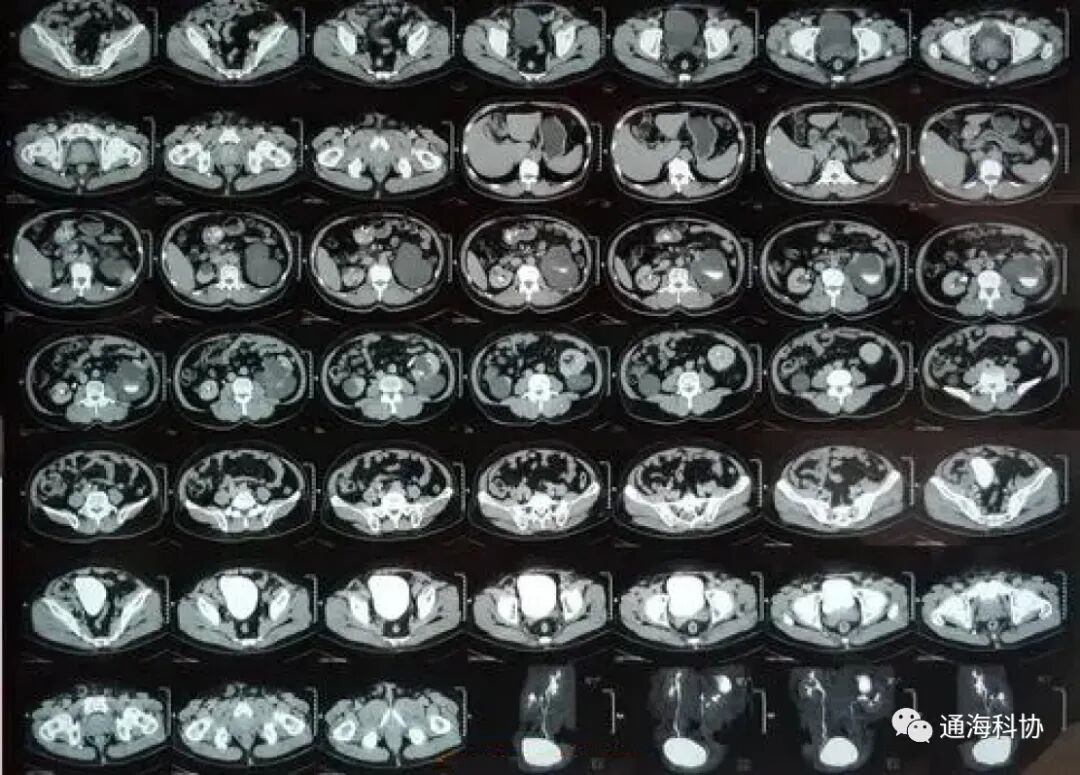

CT检查

可以看到病灶细节,精确度高,诊断结果确定度更高,是确诊头部、胸部、心脏、骨骼四肢等部位疾病的首选;但部分骨骼伪影较多,影响周围软组织结构的显示,如颅底部及椎管等,而且受呼吸运动影响,容易漏诊小的病灶,如肺部肝部小病灶等。b超md是什么意思ct、核磁、b超有什么区别,工作原理是什么?看完涨知识_https://www.jmylbn.com_新闻资讯_第11张

而且X射线是对人体有伤害的高能射线,不宜长时间或频繁检查,一些有严重疾病的患者,如严重的肝肾功能不全、甲亢、哮喘、某些过敏性病变等,不适宜这种检查。